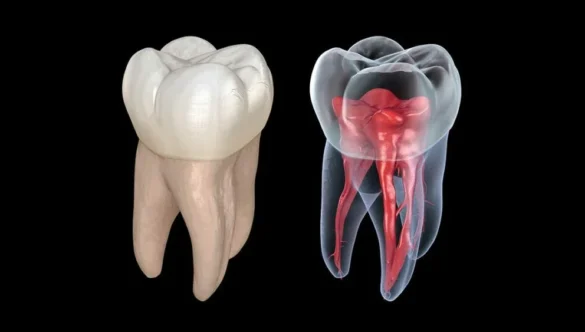

- Root canal assessment

- Bone analysis